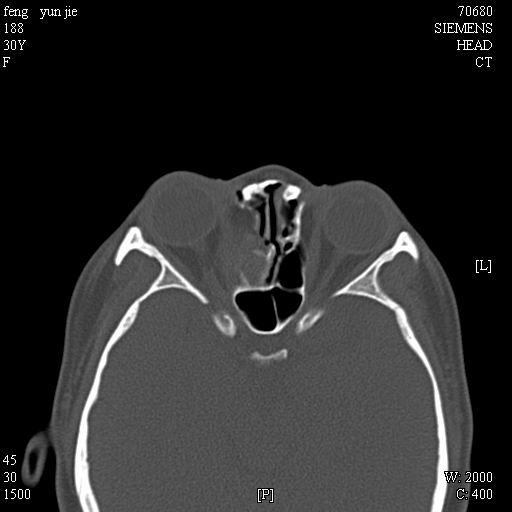

女,37岁,多年前鼻骨骨折过,现在穿刺有炎性分泌物

考虑:1、鼻骨陈旧性骨折;

2、额窦粘液囊肿(右侧水平额窦突入眶内上方)可能性大。

1)左侧鼻骨骨折(陈旧性)。2)双侧额窦及双侧筛窦炎症,伴右侧额筛窦黏液囊肿突入右侧眼眶。